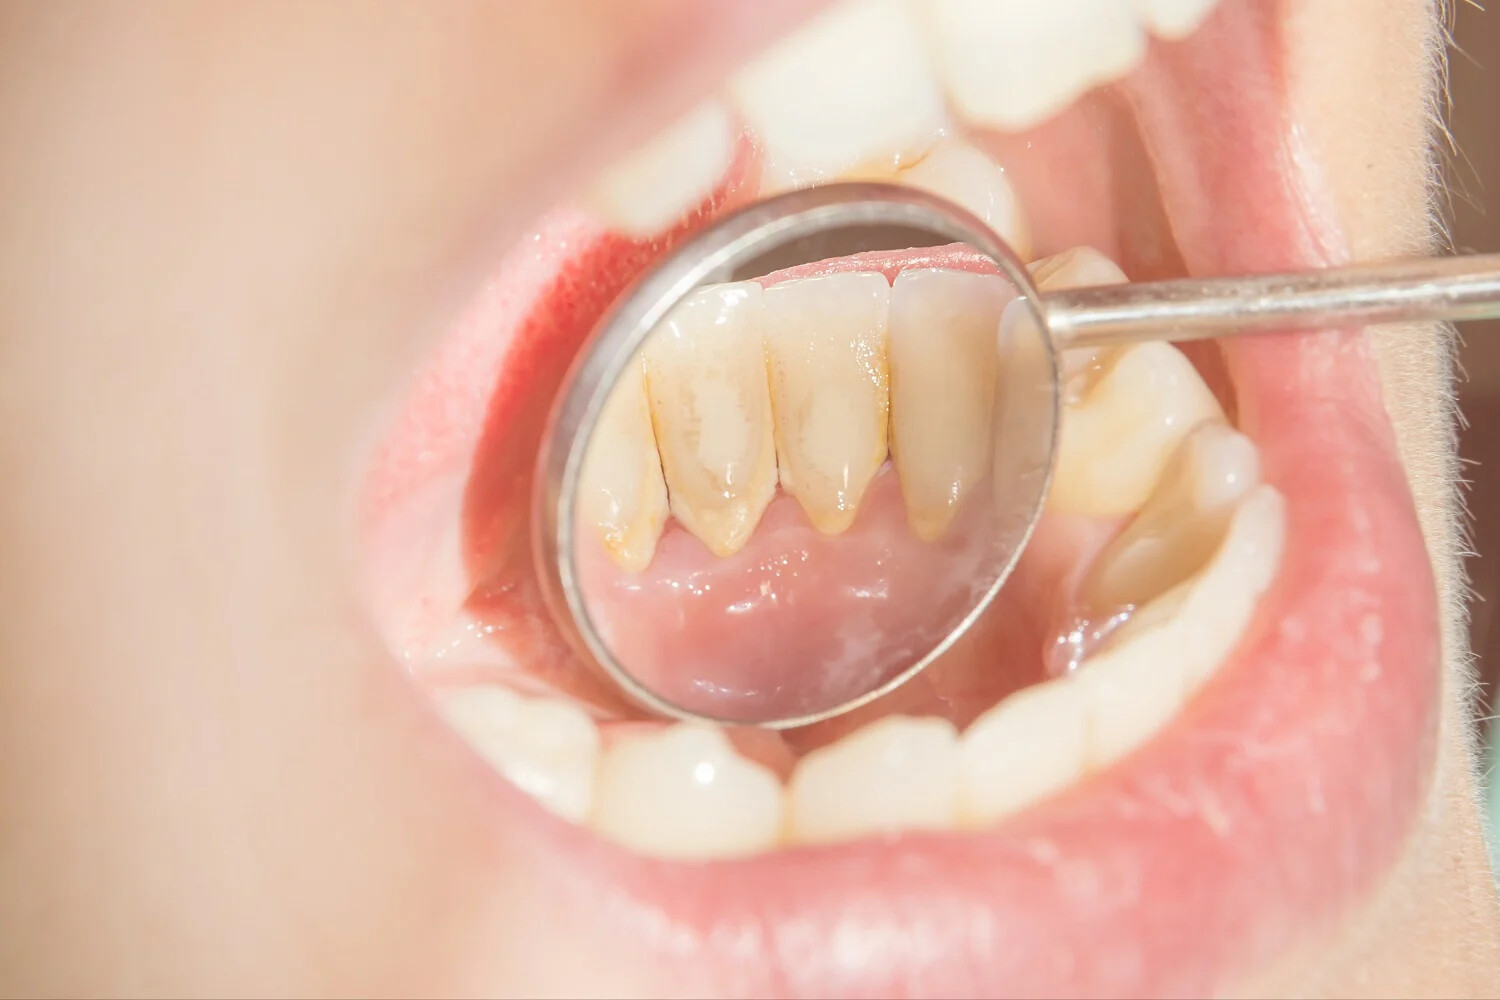

Cleaning between your teeth removes food debris and plaque, preventing cavities and gum disease. If plaque isn’t cleaned, it hardens into tartar that requires a dental professional's help to remove. Food matter that is not adequately removed will contribute to bacterial growth and tooth decay.

Mouthwash achieves these oral health benefits by helping to control plaque, which is a thin film of germs that builds up on your teeth. When plaque isn't removed, it eventually hardens into tartar. The American Dental Association (ADA) reports that mouthwash can actually slow down the formation of tartar, too.